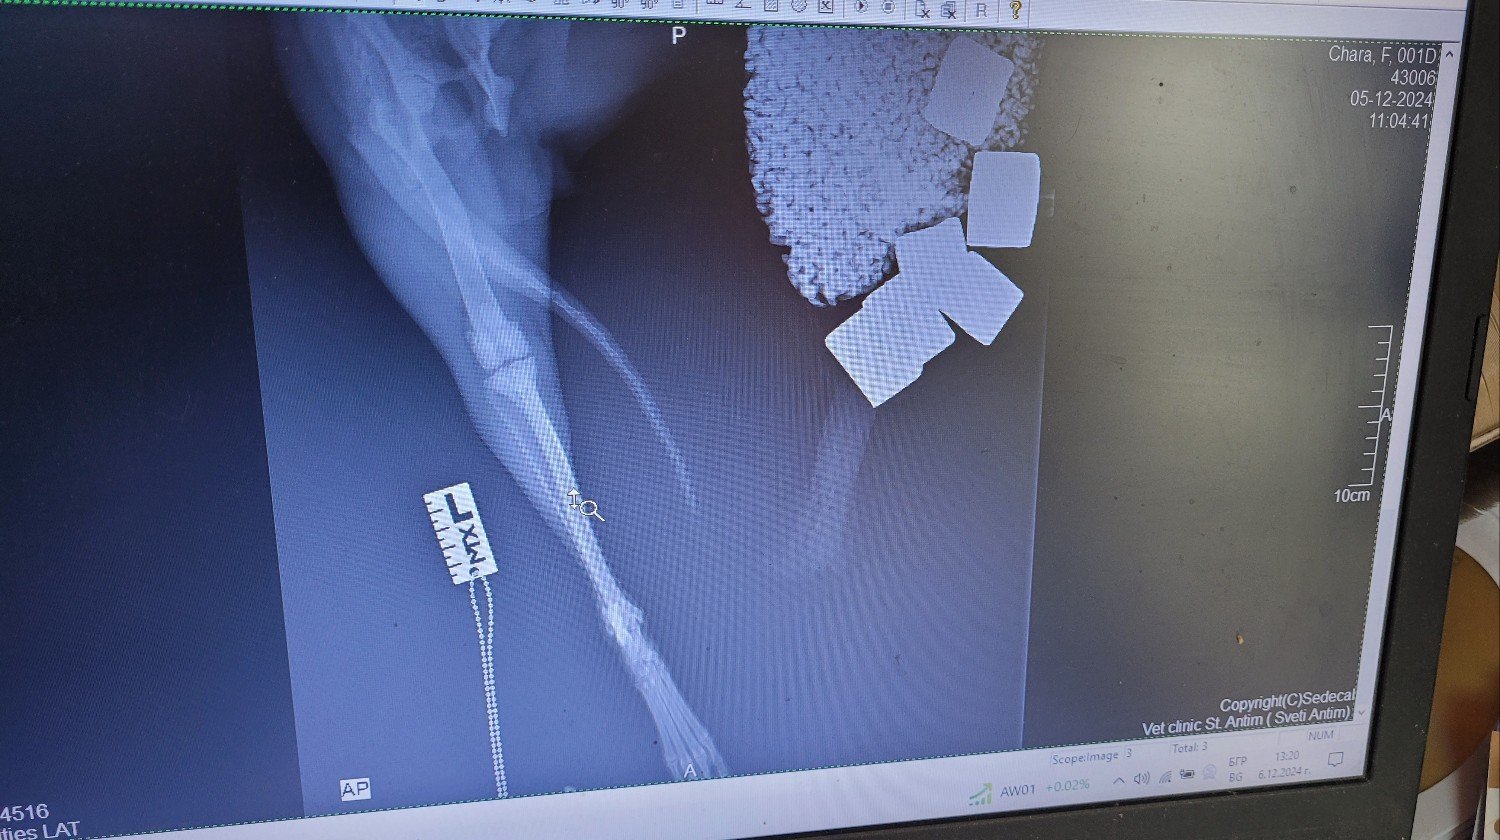

Ora è con noi da 3 mesi e oggi dovevamo fare una radiografia alle zampe e alla colonna vertebrale, poiché a volte zoppica leggermente con la zampa posteriore sinistra e mostra lievi segni di dolore.

È emerso che all'età di 1 o 2 mesi aveva una frattura alla zampa posteriore superiore che è guarita in modo non ottimale senza alcun trattamento. Di conseguenza, l'osso è un po' più corto e un po' curvo e il tendine esterno del ginocchio è allentato, per cui la sua rotula va verso l'interno della gamba. Questa situazione deve essere corretta con un intervento chirurgico, poiché il cane è ancora molto giovane e diventerà un handycapped molto presto nella sua vita. Al momento ha circa 8 mesi.

Non posso caricare molto qui, ma potete controllare il mio account TikTok Shushka1781 per vedere altre cose di Chara e Kalina-Bubka. Cercherò di caricare le radiografie in modo che possiate vederle.